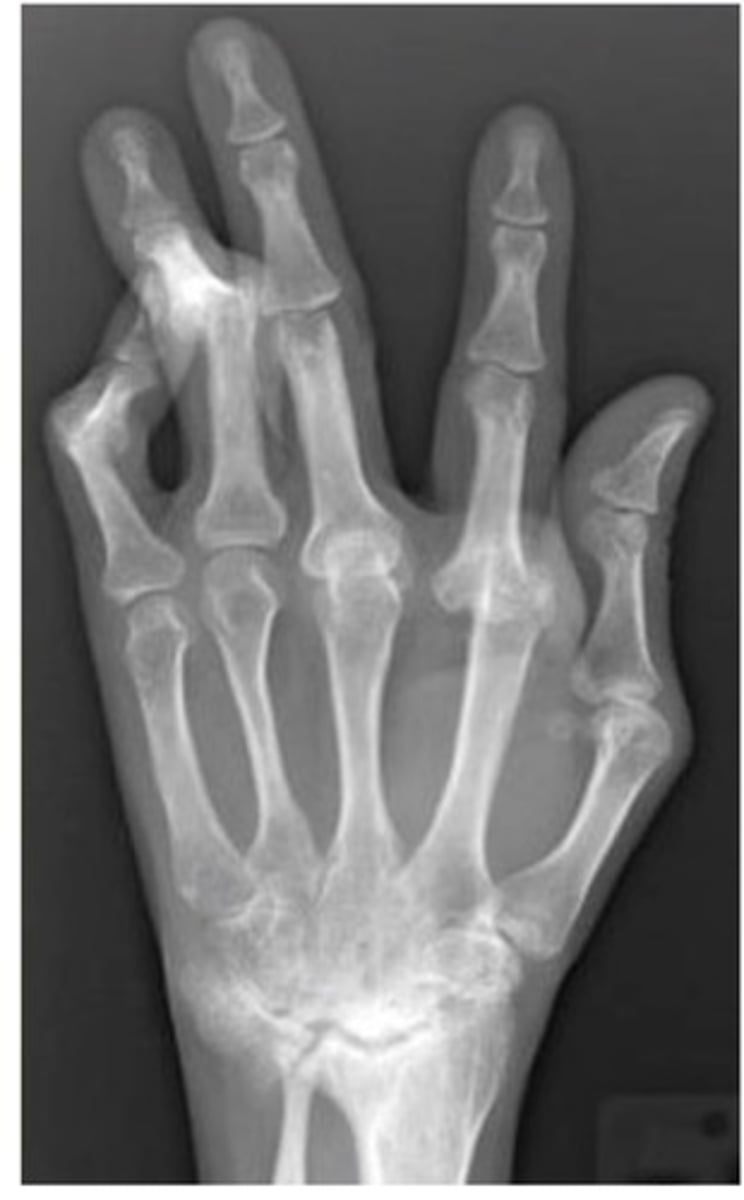

What diagnosis is this?

Psoriatic Arthritis